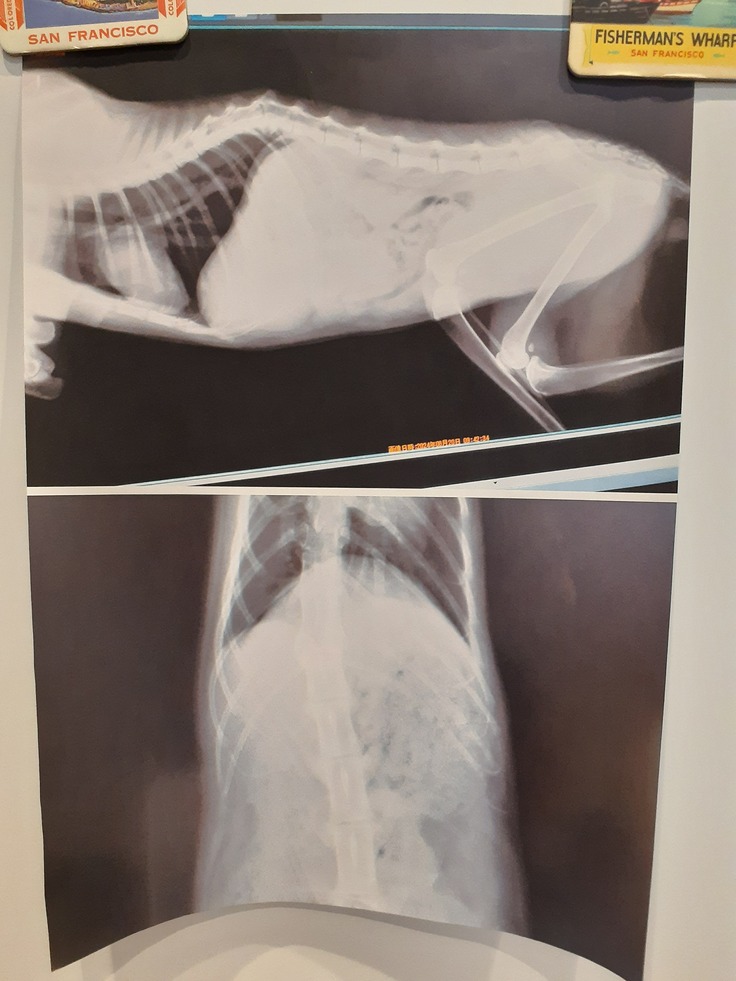

そして【そあら君】

22日夜遅くに驚くほどの血尿がありました。

下半身不随の子は尿トラブルが多いのにもかかわらず、本人は感覚がありませんので、騒いだりはしません。一般的に多頭ですと尿や便の変化について飼い主が気づくことは難しいですが、こういう子の場合、オムツを何度も替えますので案外早期発見してあげれます。

そして、膀胱炎や、結石と絞ることも容易です。

今回は前日に尿が多かったので、警戒はしていました。

ただ驚く血尿だったので朝一番に病院へ行ってきました。

エコー、尿検査をして、膀胱が汚れていること、ちょっと詰まってしまったこと、雑菌が繁殖していることが分かりました。

抗生剤等を混ぜ込んだ液体の投薬をいただいてきました。

1週間後に尿検査を予定しています。

今の時期はどの猫も膀胱炎になりやすいものの、オムツをしている子はさらになりやすい。

お尻洗いも頻繁に、オムツ替えも頻繁にしてケアを続けていきます。

以下【そあら君】のファイルです。